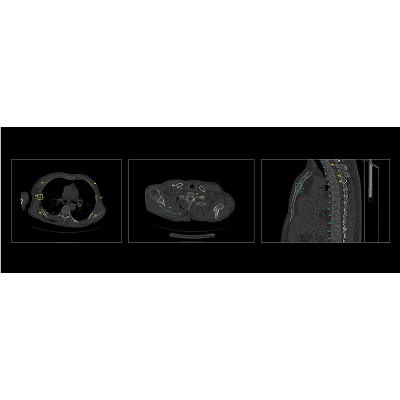

联影智能CT骨折智能分析系统具备“精确定位,秒级骨折检出,直观提示病灶,精细优化工作流”等一系列特点。基于深度学习的方法,自动完成肋骨、椎骨定位与计数,智能完成肋骨、椎骨、锁骨、肩胛骨、胸骨骨折检出与分类。同时,系统还提供MPR三视图、VR图、3D MIP、CPR、SCPR图像的全肋骨展开图、局部动态图等多种阅片视图,一键自动呈现骨折最佳视角,让骨折一目了然,细微骨伤“无处遁形”,辅助医生快速、高效、精准地完成骨折的诊断,避免错诊和漏诊。